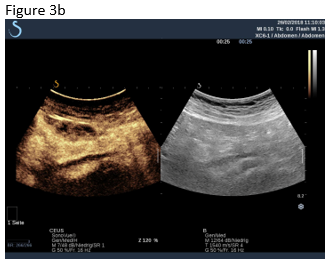

Figure 1: B-mode ultrasound using low frequency (a) and high frequency (b) revealed an isoechoic mass with a hypoechoic circumference. The mass was not adher-ent to the colon. Contrast enhanced ultrasound using low frequency (c) and high frequency (d) revealed that it was a non-enhancing segment of the omentum. Strain elastography showed that the lesion was stiffer than its sur-rounding tissue.

Figure 3: A follow up examination few weeks later revealed partially revascularised omental tissue in a now asymptomatic patient (a,b). Shear wave elastography is shown where there is now only relatively soft (inflammatory) tissue (c).